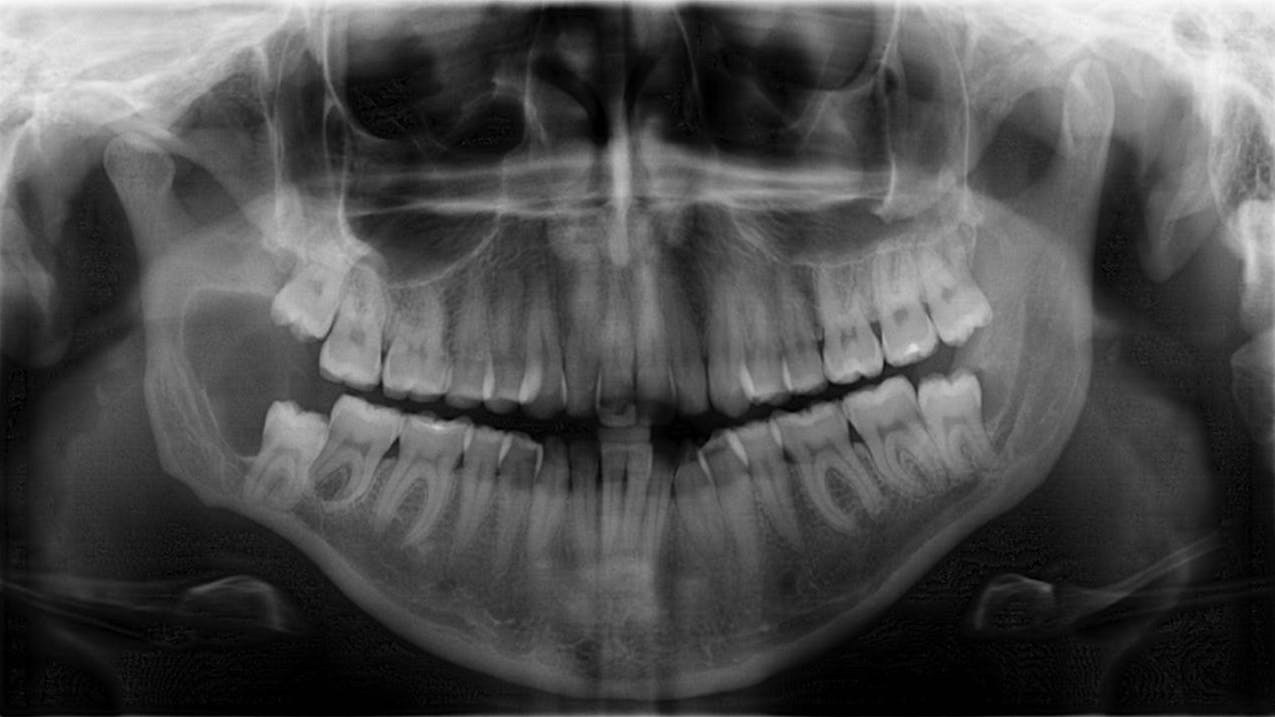

I challenge you to check out our pathology feature today! I can tell you that if my patient’s panoramic film looked like the one in the case study, I would be sweating a little bit. Learn how to navigate similar potential lesions by reading below.

🔍 Pathology case: Dangerous lesion if left untreated